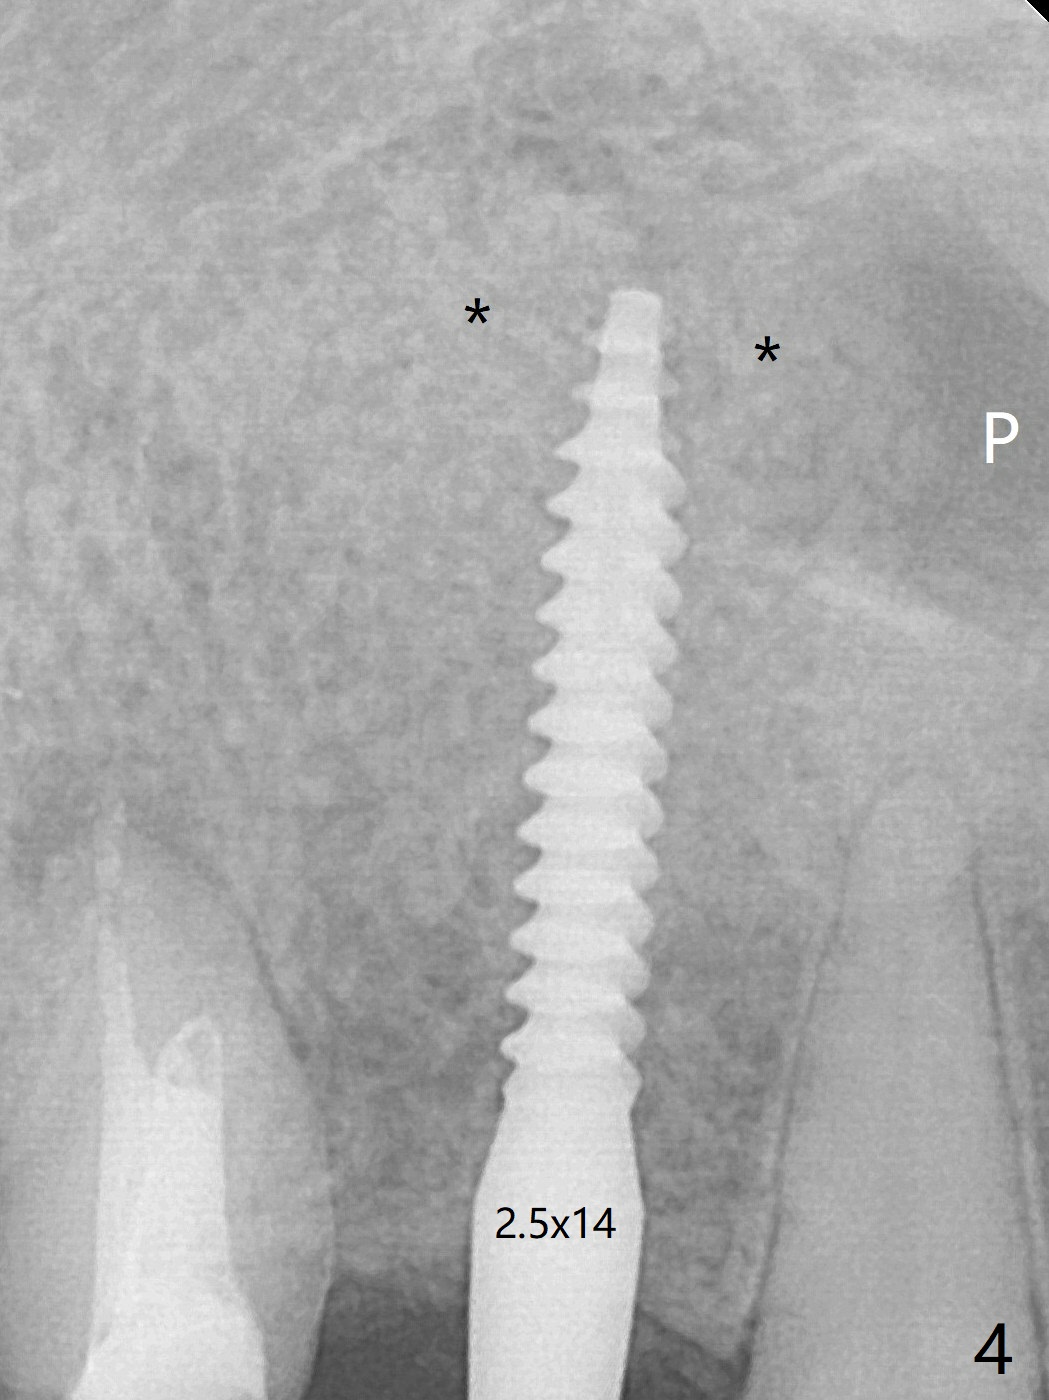

The incision is closed with suture following Osteogen plug placed in the most coronal portion of the socket (Fig.4 P) and allograft (*) in the remaining socket around the apical portion of the implant as well as palatal.  There is no bone loss around the implant 3.5 months postop (Fig.8).  The patient returns for impression 5 months postop; there is bone around the apex of the implant (Fig.12 *).  The hard and soft tissues remain healthy when final restoration is delivered (Fig.13,14).